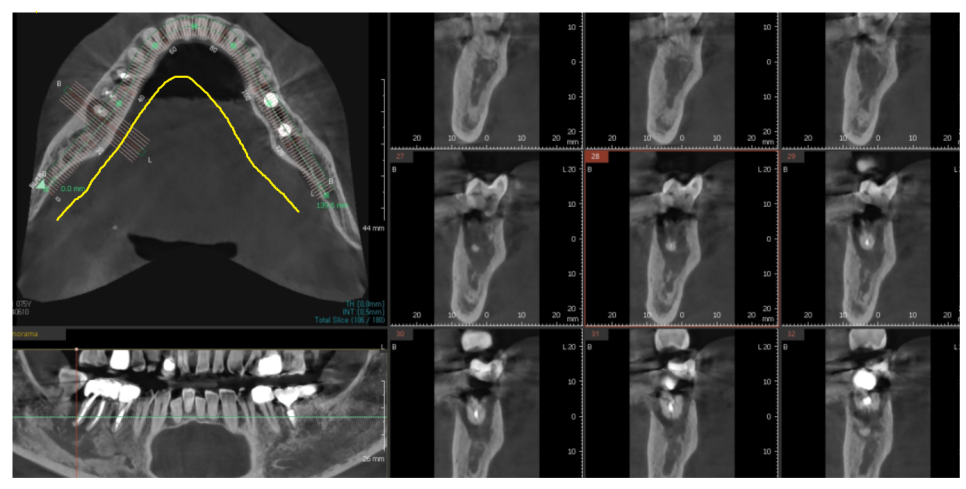

첫번째, 정밀한 진단

뼈의 밀도 , 신경의 위치, 치아 배열 정밀한 파악이 가능합니다.

3차원적 관계를 ct를 통해 확인이 가능합니다.

앞, 뒤, 좌, 우, 옆

360도 돌려가며 파악이 가능합니다.

정밀한 진단으로 수술 가이드 제작이 가능하다.

정확한 위치에 심을 수 있도록 보조해줍니다.

수술의 오차를 최소화하며, 수술 시간을 단축시켜 환자의 불편함을 줄여줍니다.

수술이 더 정확하고 안전하게 진행되는거죠~